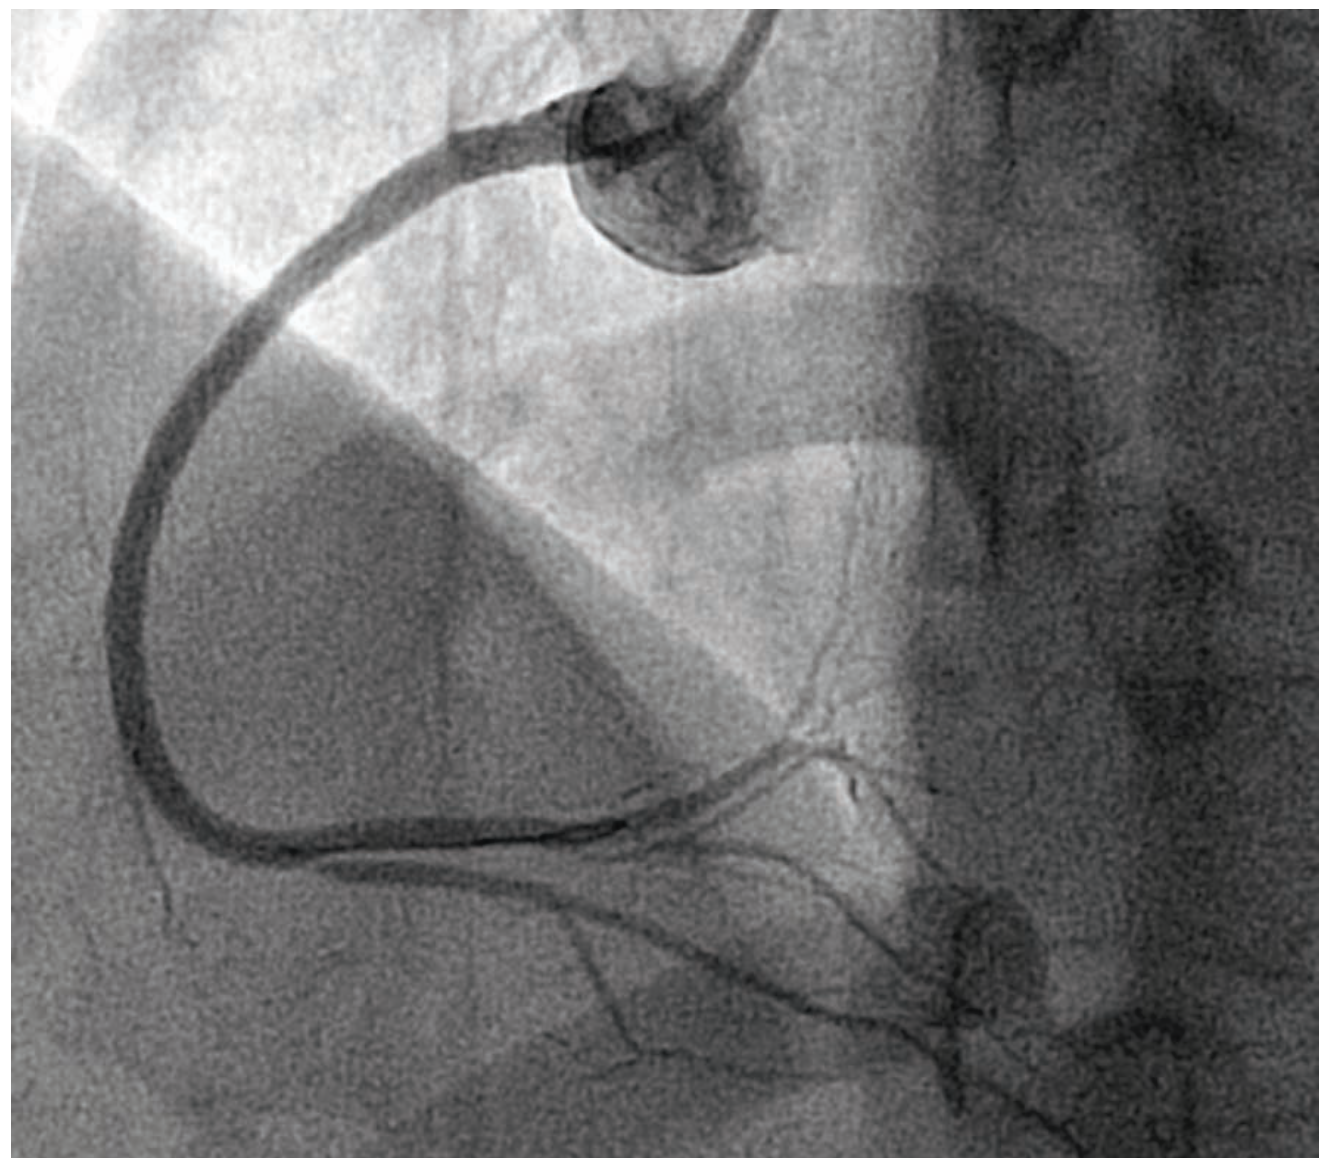

Coronary angiography demonstrated an unobstructed left main, and normal left anterior descending (LAD) artery and left circumflex (Figure 2). The right coronary artery (RCA) had an intraluminal defect extending from the ostium to the distal vessel (Figure 3, Video 1). Optical coherence tomography (OCT) was performed to further delineate this finding, and showed multiple channels with preserved intima and no evidence of plaque rupture (Figure 4, Video 2). Based on OCT, the diagnosis of woven coronary artery (WCA) was established. The decision was made to proceed with percutaneous coronary intervention (PCI) of the RCA with 3 overlapping drug-eluting stents from distal to proximal vessel (Figure 5). Post-PCI OCT was done and showed appropriate stent expansion. The patient was discharged on dual antiplatelet therapy (DAPT) in a stable clinical condition.

In our case, the mottled, hazy appearance of the RCA raised the possibility of dissection versus recanalized thrombus, based on angiography. Wiring can be particularly challenging given the multiple channels. As such, a hydrophilic guidewire with polymer coating (Hi-Torque Pilot 50, Abbott Vascular) was used, along with meticulous handling of the torque device, in order to negotiate the lesion safely. OCT was crucial to refute other diagnostic possibilities and establish the definitive diagnosis of WCA. Although WCA is usually considered a benign entity, acute coronary syndrome and even sudden cardiac death have been reported as possible sequelae.3 In our patient, the lesion extended from the ostial RCA to the distal vessel and before the bifurcation. Given the patient’s ongoing chest pain and rising cardiac biomarkers, PCI was warranted.